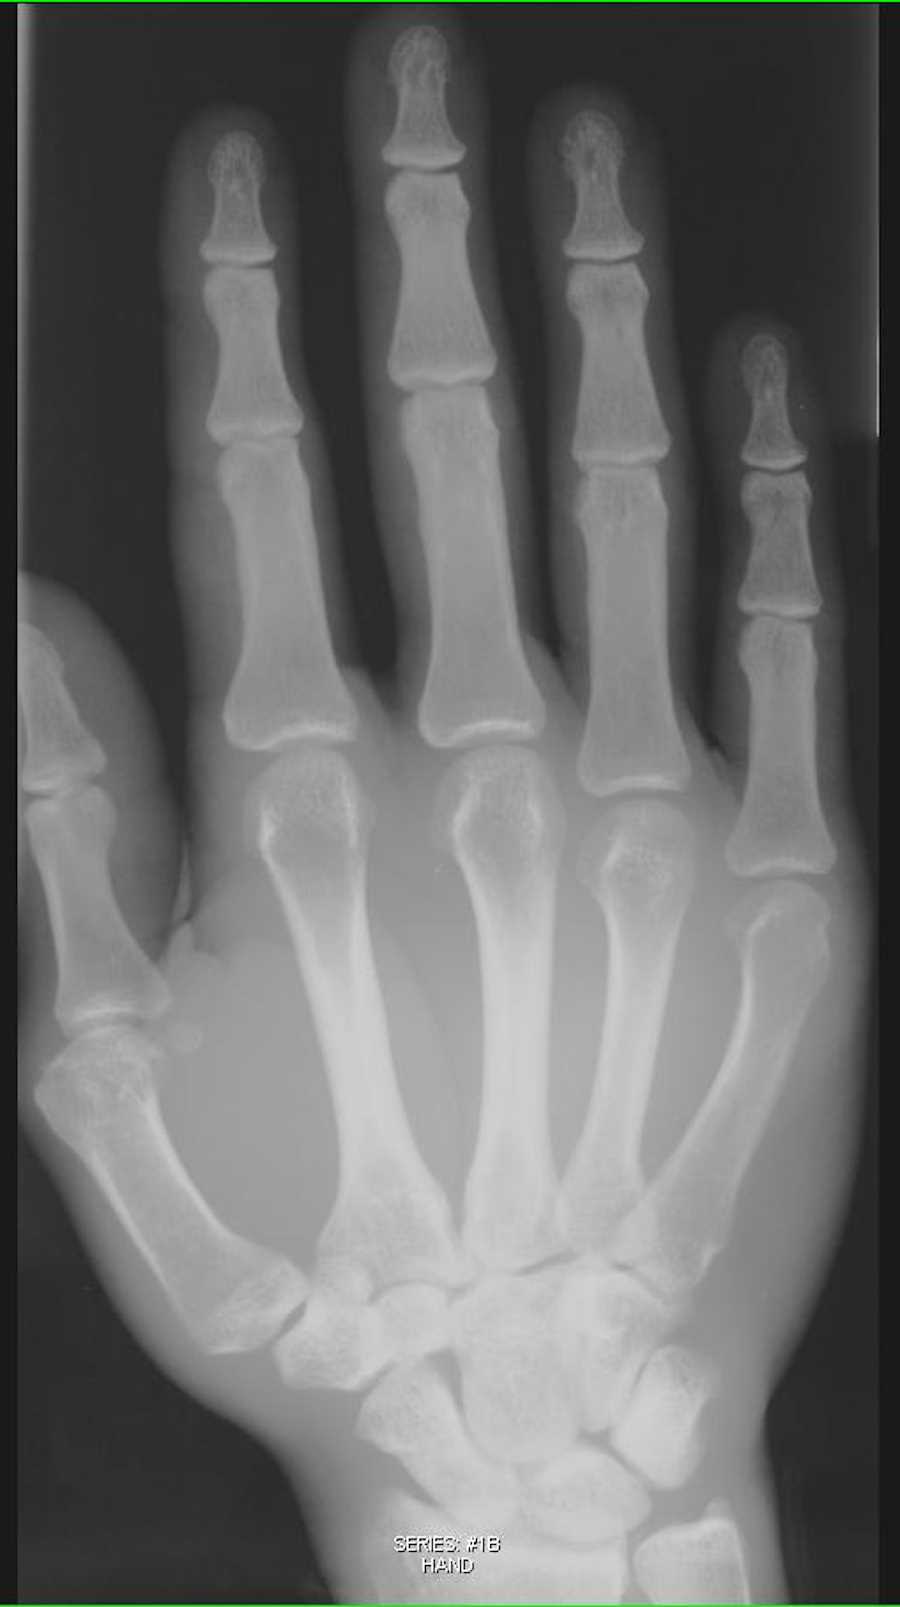

Hand X Ray Showed Soft Tissue Swelling Around The Pro vrogue.co Soft Tissue Damage On X Ray In an emergency, your x. If you have a fracture. Mri thus helps detect injury to tendons, ligaments, cartilage, and muscle. A radiologist typically views and interprets the results and sends a report to a member of your healthcare team, who then explains the results to you. Soft Tissue Damage On X Ray.

Hand X‐ray; soft tissue swelling, no fracture or dislocation, no Soft Tissue Damage On X Ray Mri thus helps detect injury to tendons, ligaments, cartilage, and muscle. In an emergency, your x. A radiologist typically views and interprets the results and sends a report to a member of your healthcare team, who then explains the results to you. If you have a fracture. Soft Tissue Damage On X Ray.

Xray Hand with soft tissue swelling X Rays Case Studies CTisus CT Soft Tissue Damage On X Ray If you have a fracture. Mri thus helps detect injury to tendons, ligaments, cartilage, and muscle. In an emergency, your x. A radiologist typically views and interprets the results and sends a report to a member of your healthcare team, who then explains the results to you. Soft Tissue Damage On X Ray.